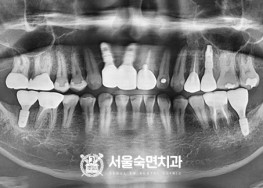

임플란트-치료-전후사진